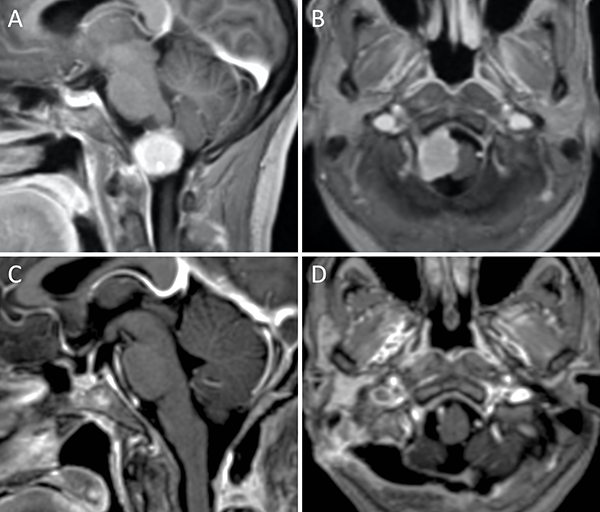

Figura 4. Meningioma petro-clival. A-B: RM preoperatoria; C-D: RM postoperatoria.